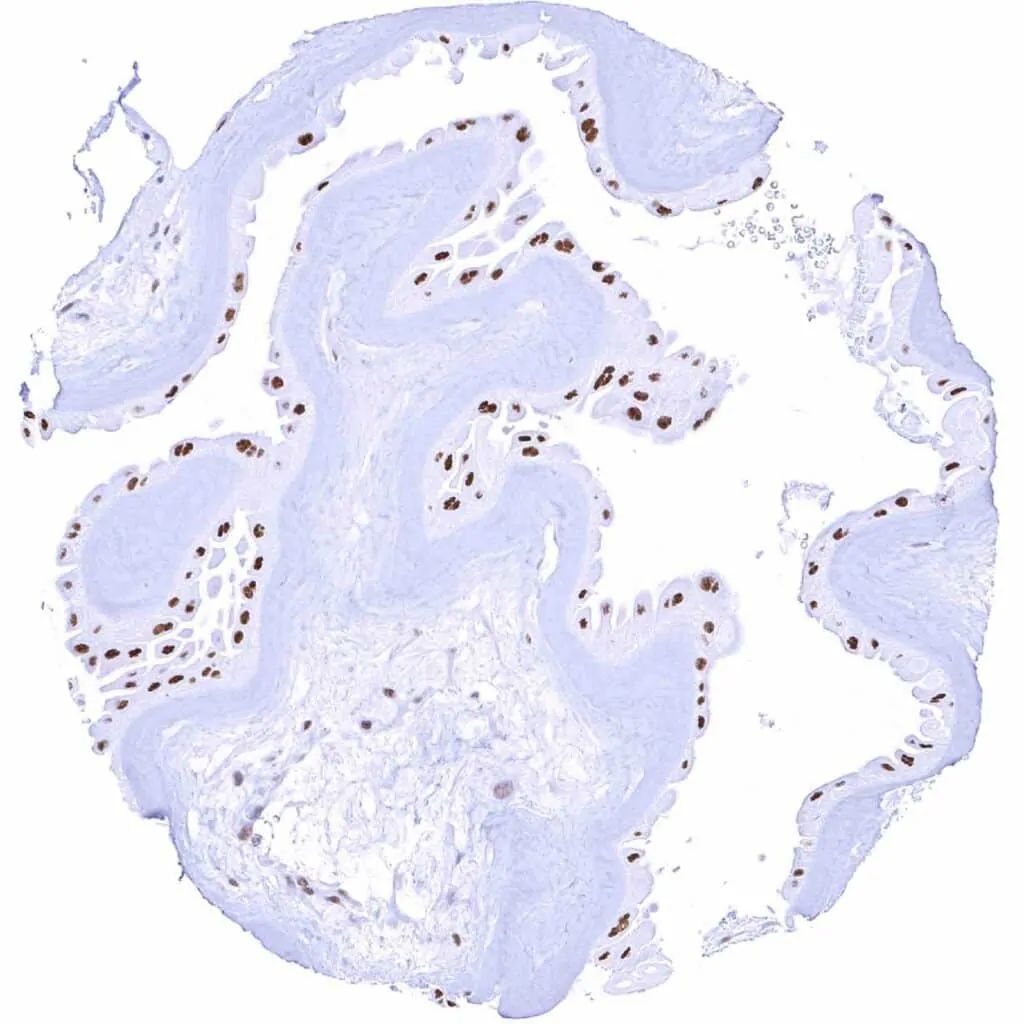

Esophagus, squamous epithelium – Weak TLE1 staining of a subset of lymphocytes and of the squamous epithelium, predominantly of the suprabasal cell layers

Tonsil, surface epithelium – Weak to moderate TLE1 staining of a subset of lymphocytes and of the squamous epithelium, predominantly of the suprabasal cell layers

Uterus, ectocervix – Moderate TLE1 staining of squamous epithelial cells, predominantly of the suprabasal cell layers